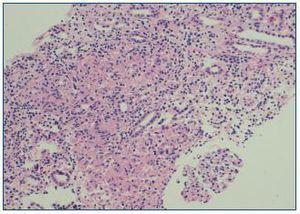

Paciente mujer de 56 años de edad sin alergias ni hábitos tóxicos y sin antecedentes médicos de interés ni tratamiento médico habitual que acude a urgencias derivada por su médico de cabecera por alteración analítica (creatinina 8 mg/dl) practicada por estudio de síndrome tóxico de 6-7 meses de evolución con pérdida ponderal objetivada de 10 kg. Aportaba analítica realizada 5 meses antes en revisión laboral en la que destacaban una Hb de 11 g/dl y una creatinina de 1,7 mg/dl. En la exploración física la paciente estaba normotensa, con palidez de mucosas; el resto de examen físicono presentó alteraciones. Analítica con Hto/Hb 28%/9,6 g/dl, urea/creatinina 192/9,4 mg/dl (FG estimado 4 ml/min), calcio 10 mg/dl. FENa 10. Proteinuria/24 horas de 0,6 g y sedimento normal. PTHi y vitamina D normal. HbsAg, VHC y VIH negativos. Estudio inmunológico: ANA, anti-ADN ,ANCA, complemento e inmunoelectroforesis normal o negativo. Rosa de Bengala y anticuerpos anti-Brucella negativos. Cultivo de Löwenstein en orina negativo. PPD negativo. ECA 189 U/l (8-52 U/l). Radiografía de tórax, ecografía abdominal y TAC tóraco-abdomino-pélvica, normales. Examen oftalmológico y otorrinológico sin alteraciones significativas. Se colocó catéter yugular y se inició hemodiálisis. Se practicó biopsia renal percutánea que presentaba 10 glomérulos, dos de ellos esclerosados, y el resto de aspecto normal, destacando, en el intersticio, abundantes granulomas constituidos por células epiteloides y células gigantes multinucleadas tipo Langhans sin presencia de necrosis (figura 1). Las técnicas histoquímicas para la detección de bacilos ácido-alcohol resistentes y para hongos fueron negativas. Se inició tratatamiento con prednisona a dosis de 1 mg/kg/día. La paciente mantuvo la diuresis conservada con correcta tolerancia a la hemodiálisis. A partir de la cuarta semana de tratamiento corticoideo observamos una mejoría progresiva de la función renal que le permitió abandonar el tratamiento sustitutivo. Actualmente, a los 4 meses de inicio del tratamiento y con una dosis de 0,3 mg/kg/día, presenta una creatinina plasmática de 2,8 mg/dl (FG 19 ml/min) con determinación normal de la ECA.

Figura 1. Cortical de riñón.